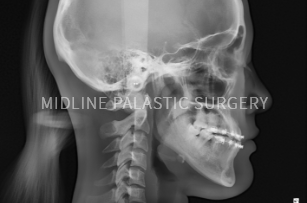

첫째, 3D-CT로 얼굴 뼈 촬영

둘째, CT, X-ray로 얼굴 뼈 전체 분석

셋째, 개개인에 맞는 섬세한 수술 계획

CT 촬영

3D-CT로 촬영한 데이터를 기반으로 얼굴뼈

전체를 정밀하게 분석하여 보다 안전하고

정확한 수술 계획이 가능합니다.